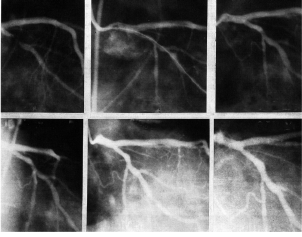

El primer seguimiento angiográfico realizado entre 30 a 60 días en ese paciente mostró un diámetro luminal mínimo de 1,63 ± 0,89 mm, y hubo una estenosis residual promedio de 46 ± 28 %. El segundo control angiográfico fue realizado en 20 arterias entre 6 y 14 meses (promedio 8 ± 1,9 meses). Todos estaban permeables durante el seguimiento con un diámetro luminal mínimo de 1,94 ± 0,62 mm y diámetro luminal residual de estenosis de 41 ± 24 %, similar a los resultados con angioplastia (P = 0,2). La pérdida tardía calculada es de 0,19 ± 0,78 mm y el índice de pérdida tardía fue 0,19 ± 0,4 mm. El diámetro luminal mínimo mostró una pérdida tardía negativa en 10 de las 22 arterias (Cuadro 1). Se observó una reestenosis angiográfica binaria (mayor a 50 % de diámetro de la estenosis) en 27,3 % de las arterias, incluyendo los 2 pacientes con una oclusión total temprana. Un ejemplo de un caso con pérdida tardía negativa a los 14 meses con dilatación en el sitio tratado se muestra en la Figura 5.

Pre Post 24 horas

1 año 2 años 3 años

Figura 5. Seguimiento angiográfico de la arteria circunfleja. Radioterapia intracoronaria gamma, angioplastia transluminal coronaria percutánea.